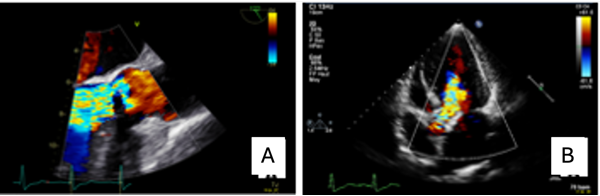

During the next four months, the catheter was flushed twice on a weekly basis and despite not infusing the patient with dialysate, about 1.85 liters of transudate ascites was drained every two days through the peritoneal catheter. Clinical examination showed large abdominal wall venous collaterals, no palpable nodes, muted cardiopulmonary auscultation, no abdominal pain nor lower limb edema at that time. Laboratory tests showed no sign of decompensated cirrhosis (serum albumin of 32 g/l (normal range: 40-49 g/l), Prothrombin time 75% (normal range: 70-100%), c-reactive protein 7mg/l (normal range: <10 mg/l), total bilirubin 1.0 mg/dl (normal range: < 1.2 mg/dl). A liver magnetic resonance imaging and CT scan ( Figure 1) revealed perihepatic ascites, central fibrosis, and preserved permeability of the supra-hepatic veins but signs of chronic obstruction of the portal vein.

Figure 1.Abdominal computed tomography revealing perihepatic and abdominal ascites. The peritoneal dialysis catheter is still in place.